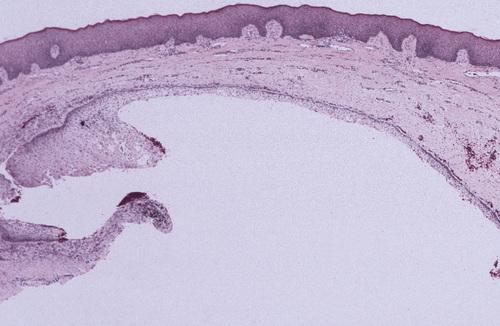

This noninflamed cyst shows a thin, nonkeratinized epithelial lining and a loosely arranged fibrous connective tissue wall.

dentigerous cyst, noninflamed